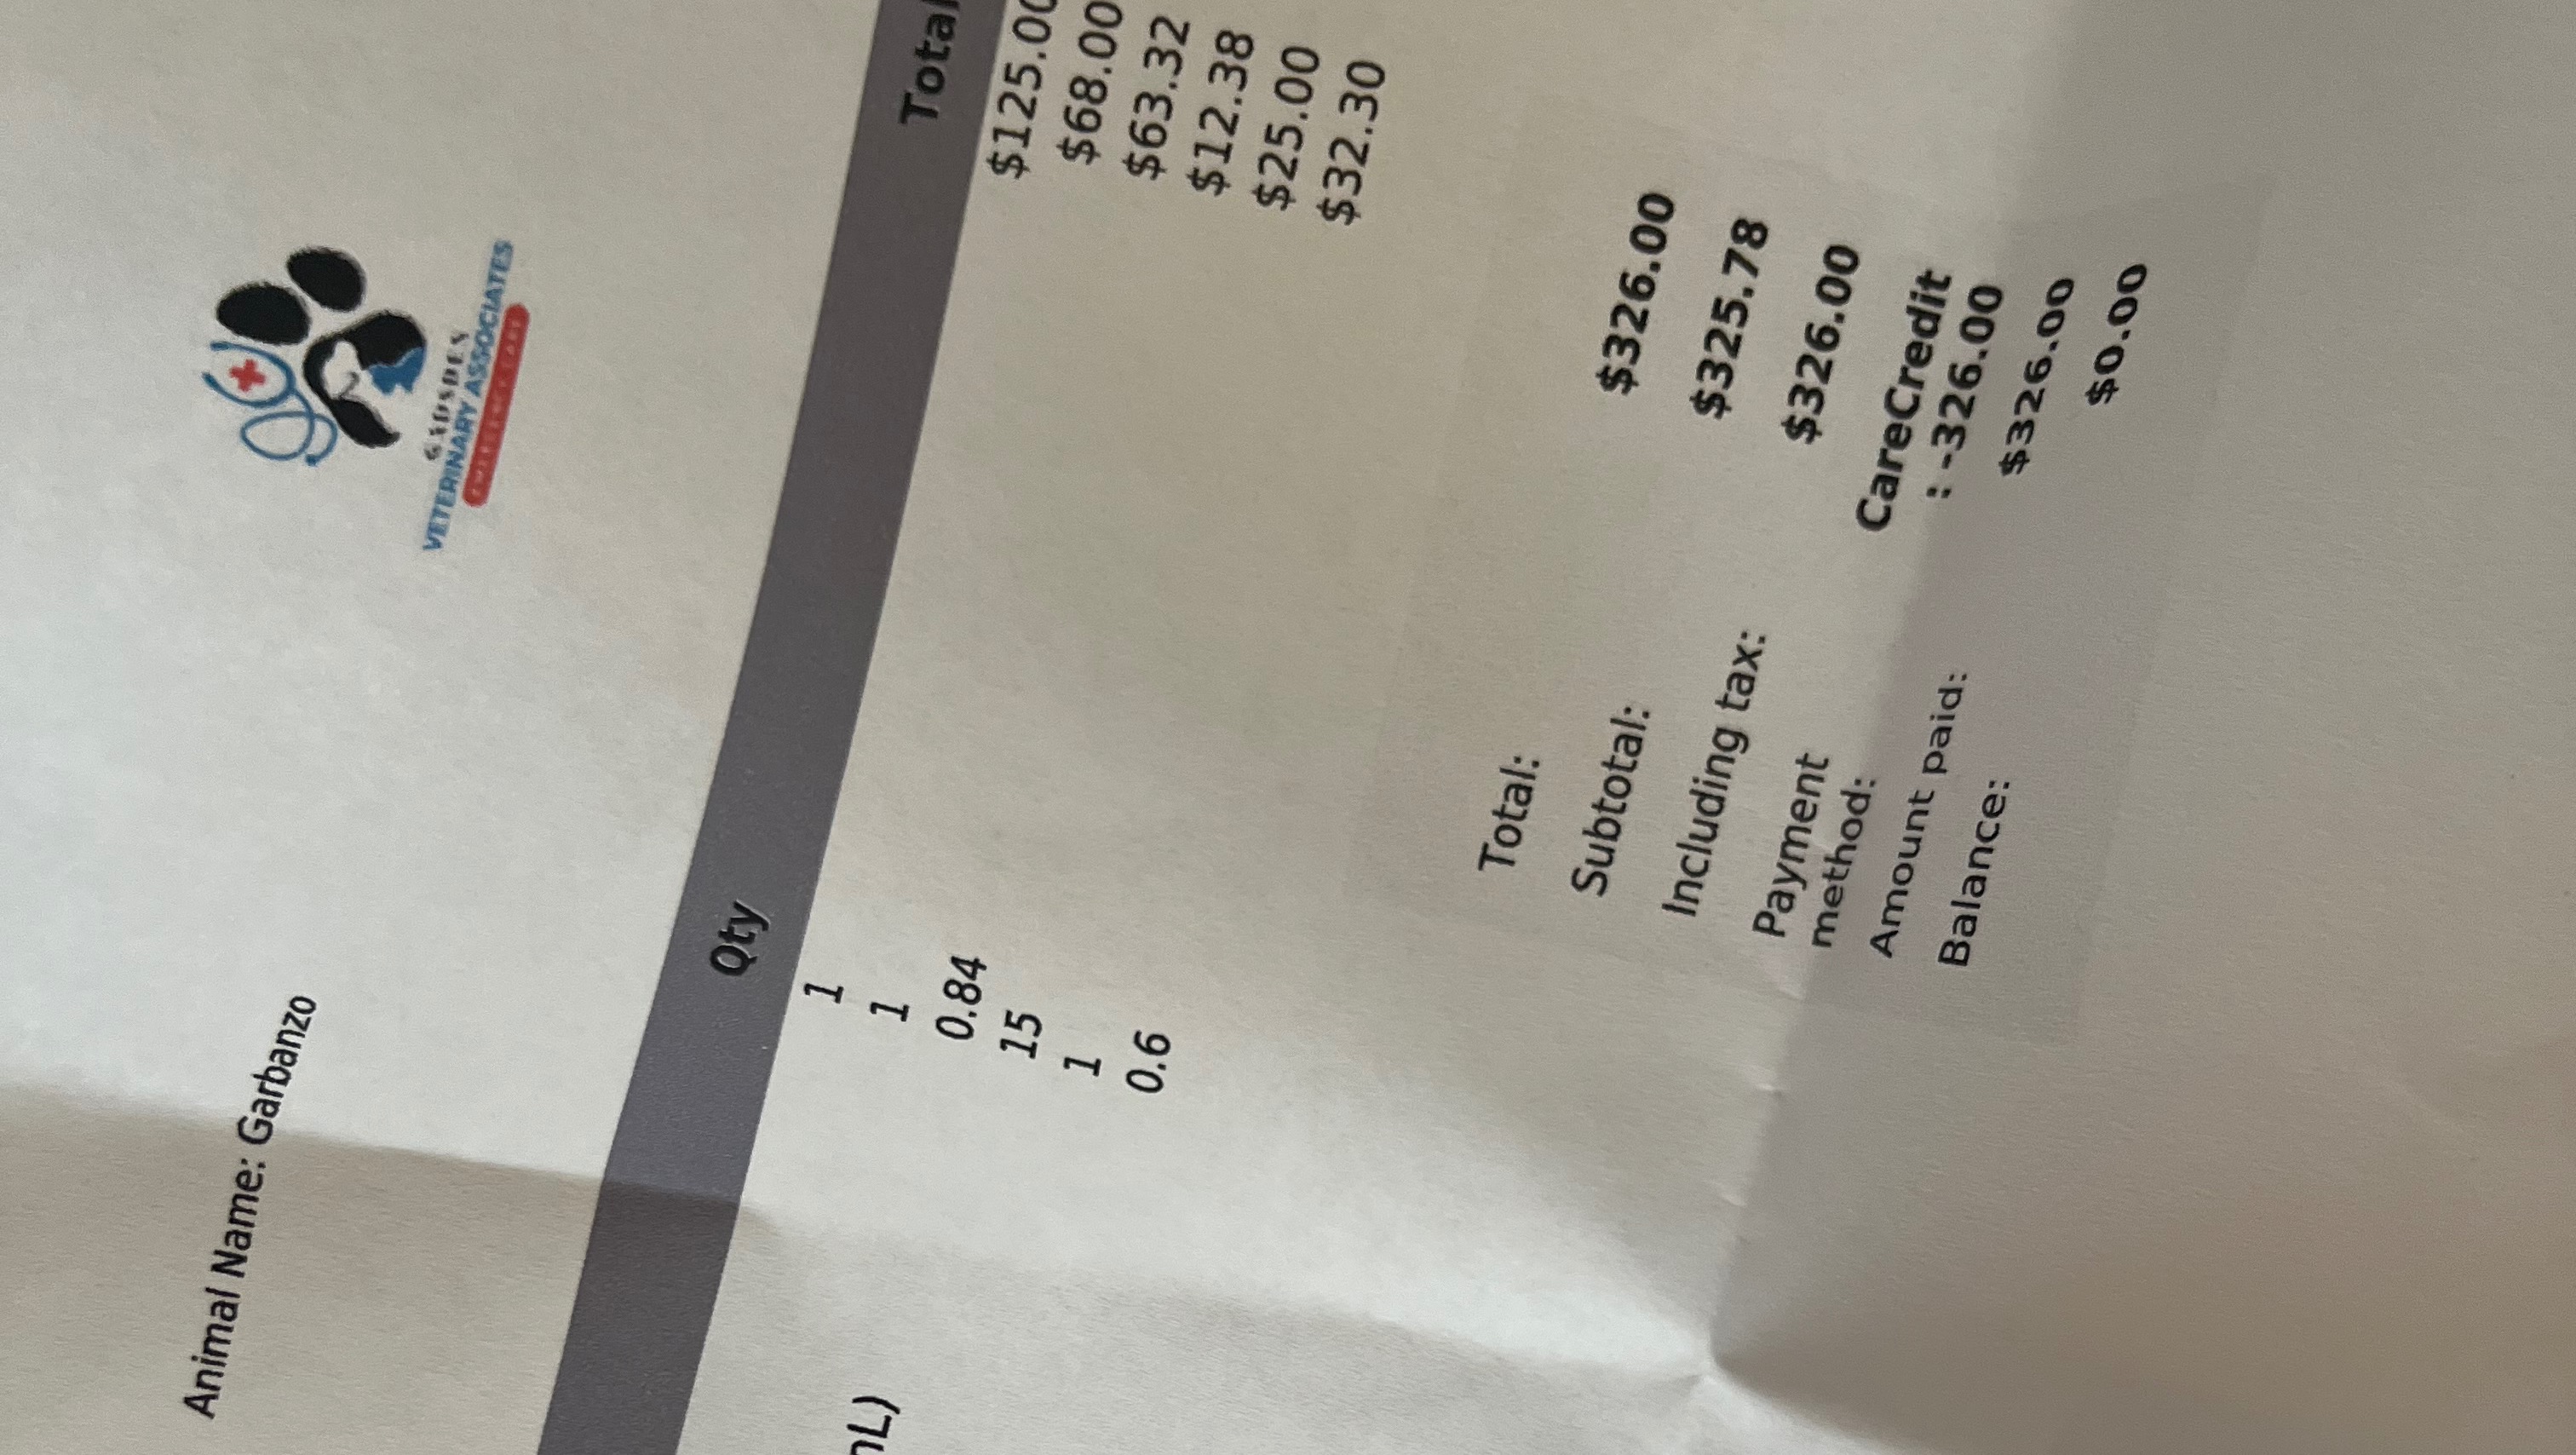

In late September, Garbo had to stay at Rainbow City Pet Clinic for five days due to a blocked urinary tract. The treatment cost almost $1,200, and though CareCredit helped cover most of it, we've continued to face escalating vet bills. Since then, Garbo has needed additional visits—2-3 more since his stay—making this situation more financially draining than we could have ever anticipated.

But by Wednesday, November 5th, Garbo's condition deteriorated drastically. He wasn’t moving, eating, or drinking. He seemed so weak and lethargic, it was heartbreaking to watch. I rushed him to the emergency vet at 2 a.m., and after a $300 emergency treatment, they drained his bladder, which was filled with bloodied urine. He was blocked.

As I write this, Garbo is still at the vet, and his bills are adding up fast—another $1,000 on top of everything else. That much was paid out of our own pockets.

Any donation, no matter how small, will go directly toward his treatment and surgery. We'll provide proof of payment for all vet bills and CareCredit charges, so you can see exactly where your donation is going.